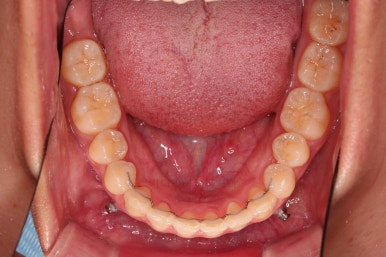

교합 양호하고 치아 사이 틈새도 잘 모아졌습니다.

특히나 틈새가 있었던 환자분의 교정치료는 재발을 할 우려가 크므로 원인 요소가 되는 부분들을 잘 찾고 개선해주며 유지장치도 좀 더 광범위하게 부착해 줍니다.

이제 부산치아교정 전후 비교를 해볼게요.

틈새가 예쁘게 모아졌고요.

교합도 좋아졌고, 앞니도 가지런해졌네요.

당연히 얼굴 모습도 마이너스 없이 예쁘게 마무리가 잘 되었습니다.

이상 미니스크류를 이용해 어금니를 전방으로 당겨오면서 틈새를 모아주었던 부산치아교정 치료사례였습니다.